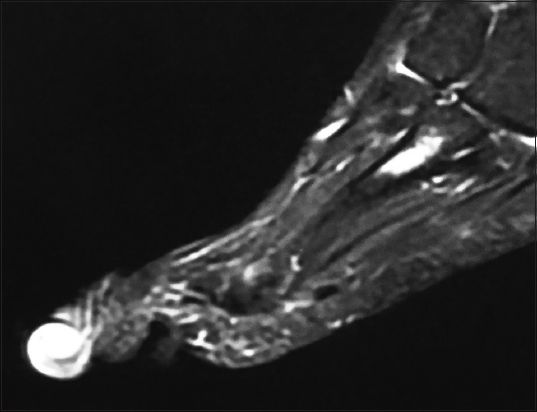

Fig. 3

Sagittal T1 MR image of the right foot shows a subungual exostosis in the third toe.